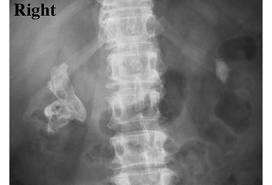

What caused this?

Upper UTI with a urea-spliting bacteria, i.e. Staph, Proteus, Pseudomonas, Klebsiella, Mycoplasma

(This is a staghorn calculus, aka struvite calculus, a complication of upper UTIs)